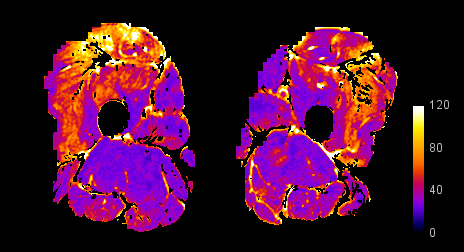

Quantitative Imaging

Expert image interpretation is predicated on knowledge and experience. The use of imaging as a biomarker in medical research could be empowered by leveraging methods and concepts that remove the subjectivity of image interpretation. For example, we have pioneered the use of muscle T2 maps, corrected for fat content, as a marker of active disease in inflammatory myopathy.